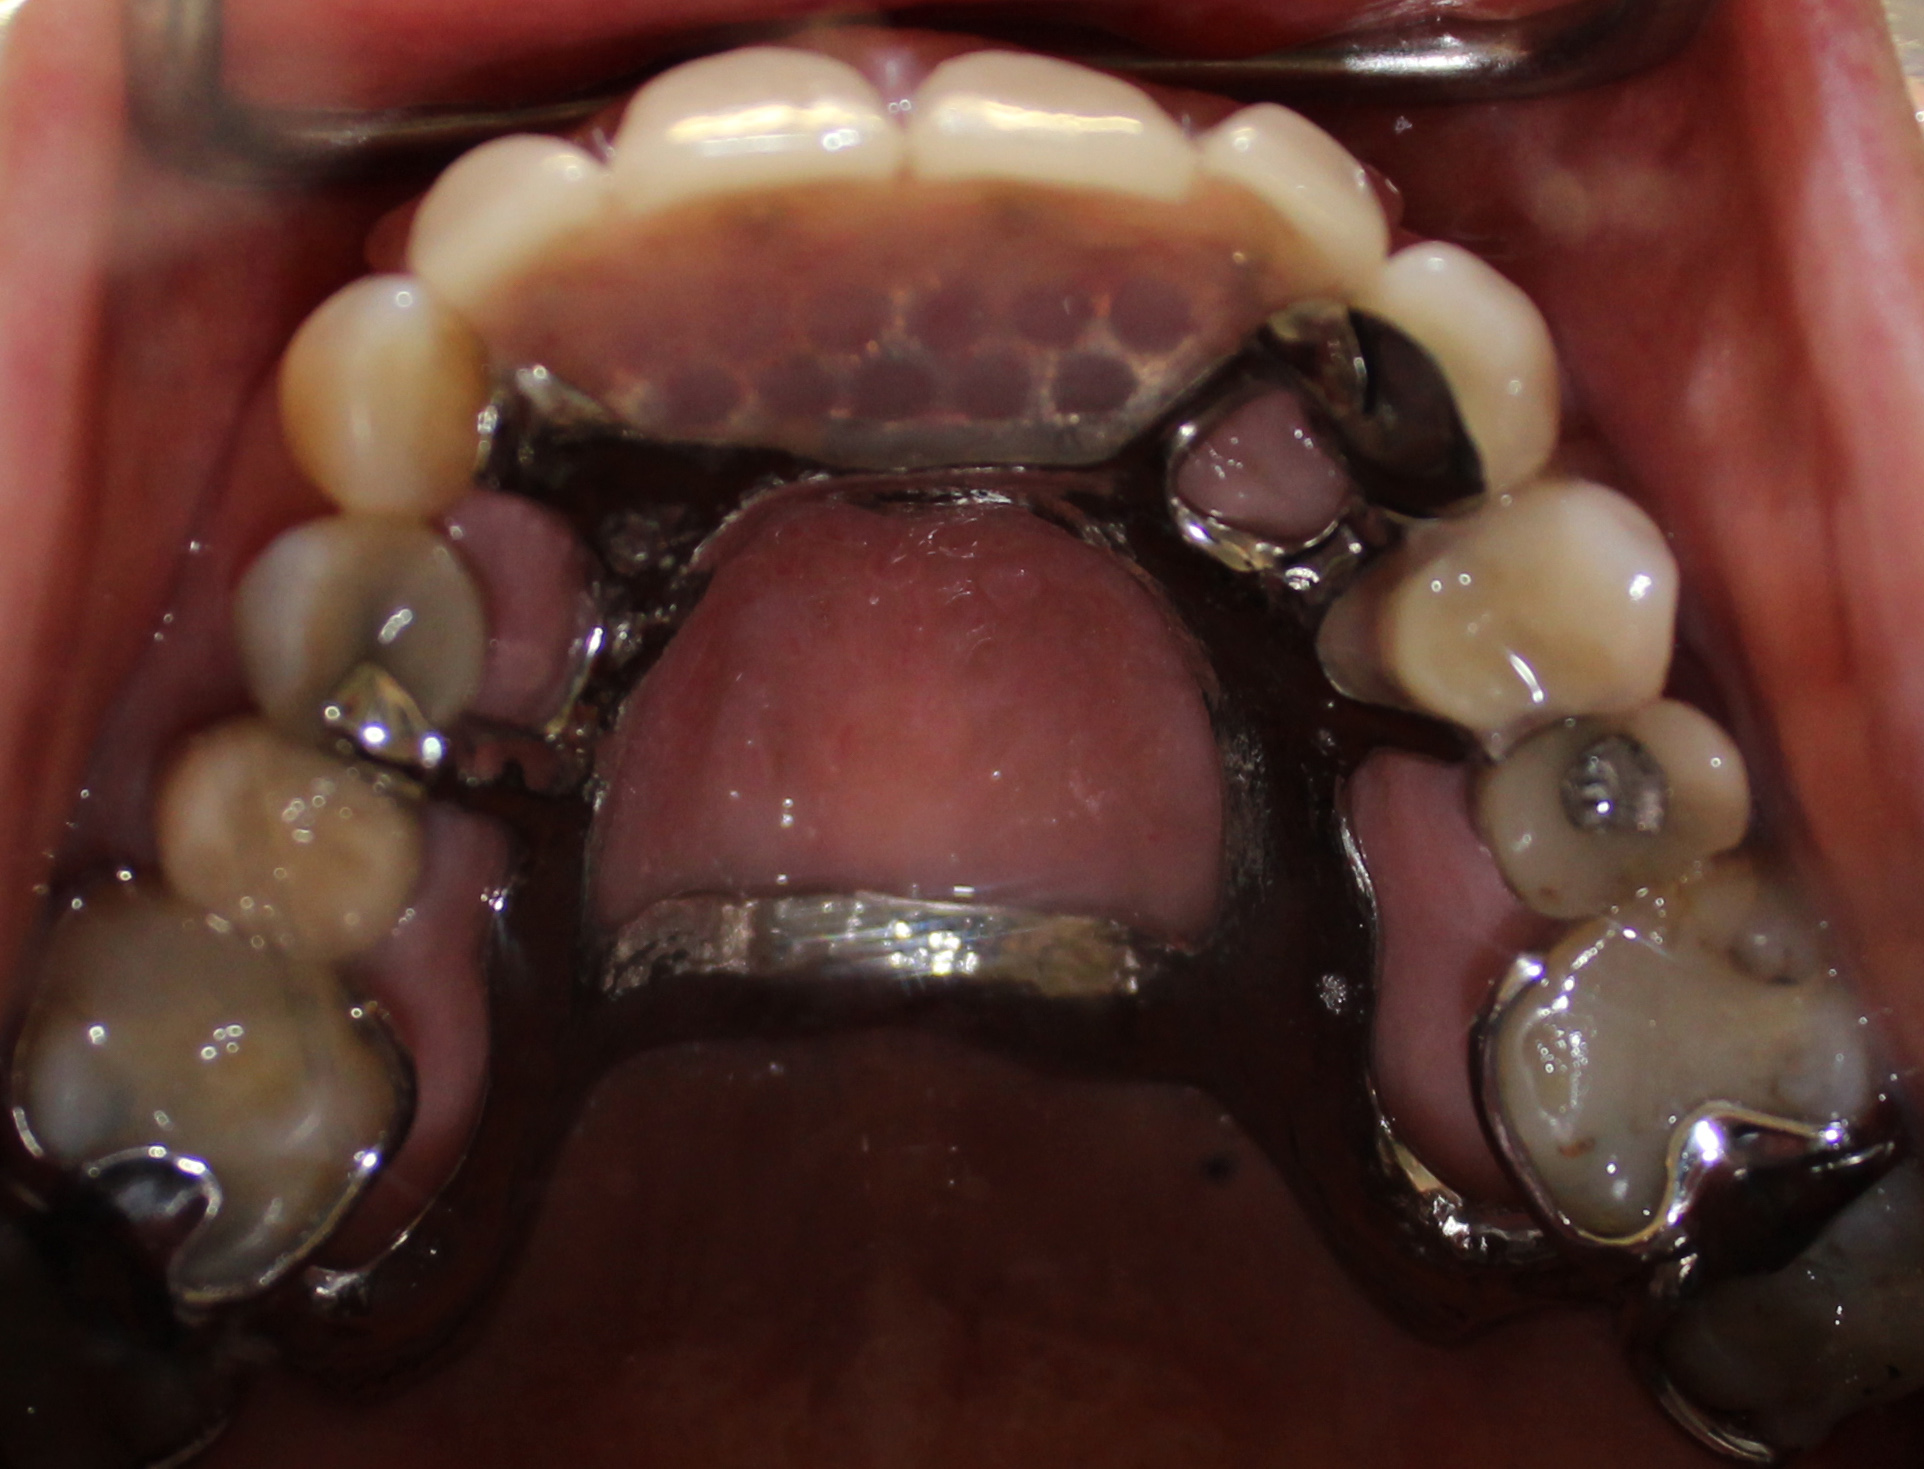

Maxillary cast partial denture and mandibular implant-supported ...

Maxillary cast partial denture | Download Scientific Diagram

Metal Partial Denture | Hummingbird Dental | Voted Top Choice Richmond ...

Cast Partial Denture in Toronto | Atlas Dental

3-case-1-metal-upper-partial-denture-in-mouth